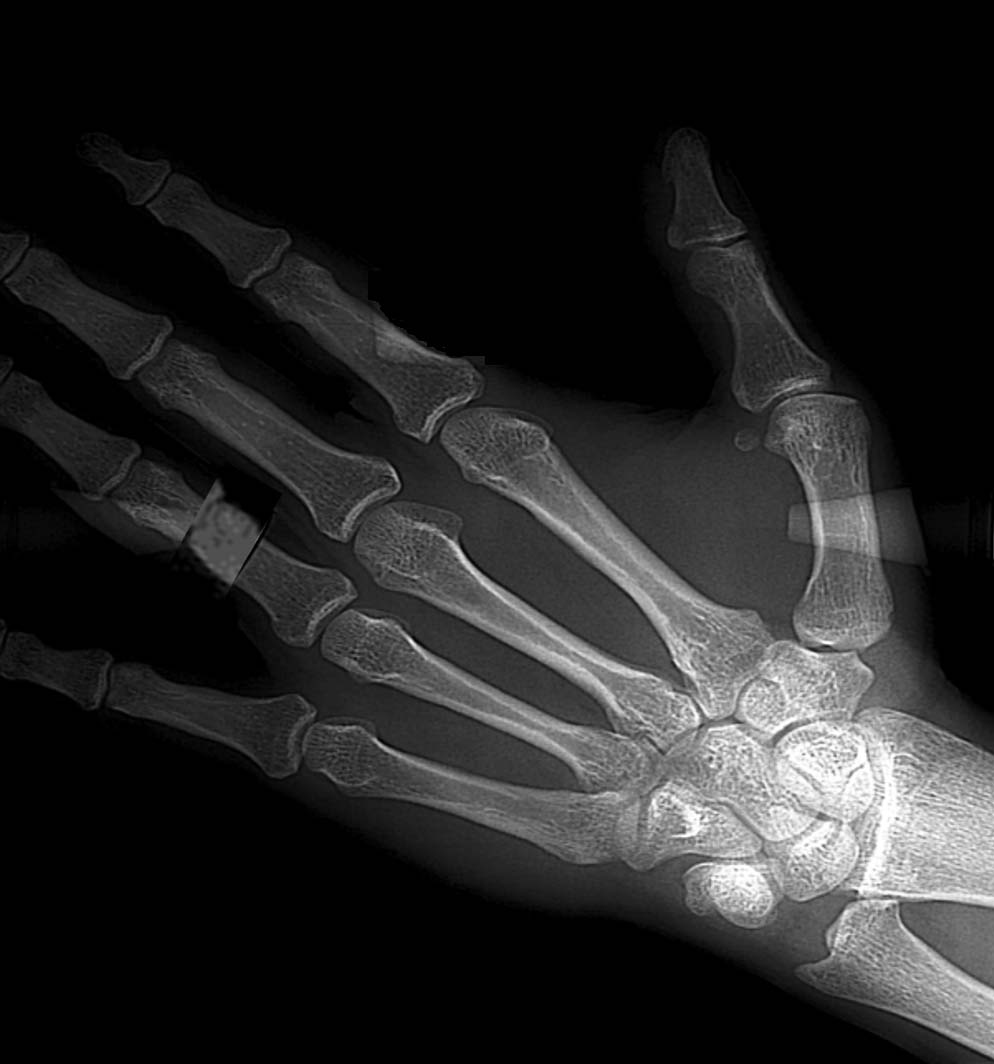

Her tanılama için her açıdan optimizasyon, minimum hacim, maksimum konfor. 8 Diyagnostik program Lateral, AP-PA veya ful kafa Submentoverte Hızlı CEPH Lateral (low dose) Carpus (El Bilek) Yeni nesil CMOS sensör ile daha fazla detay, daha iyi yumuşak doku görüntüsü sağlanır. Sefalometrik Çekim Programları Lateral Sefalometrik Anterio-Posterior Sefolometrik Submentowertex Çekim El/Bilek Çekimi (Opsiyonel)